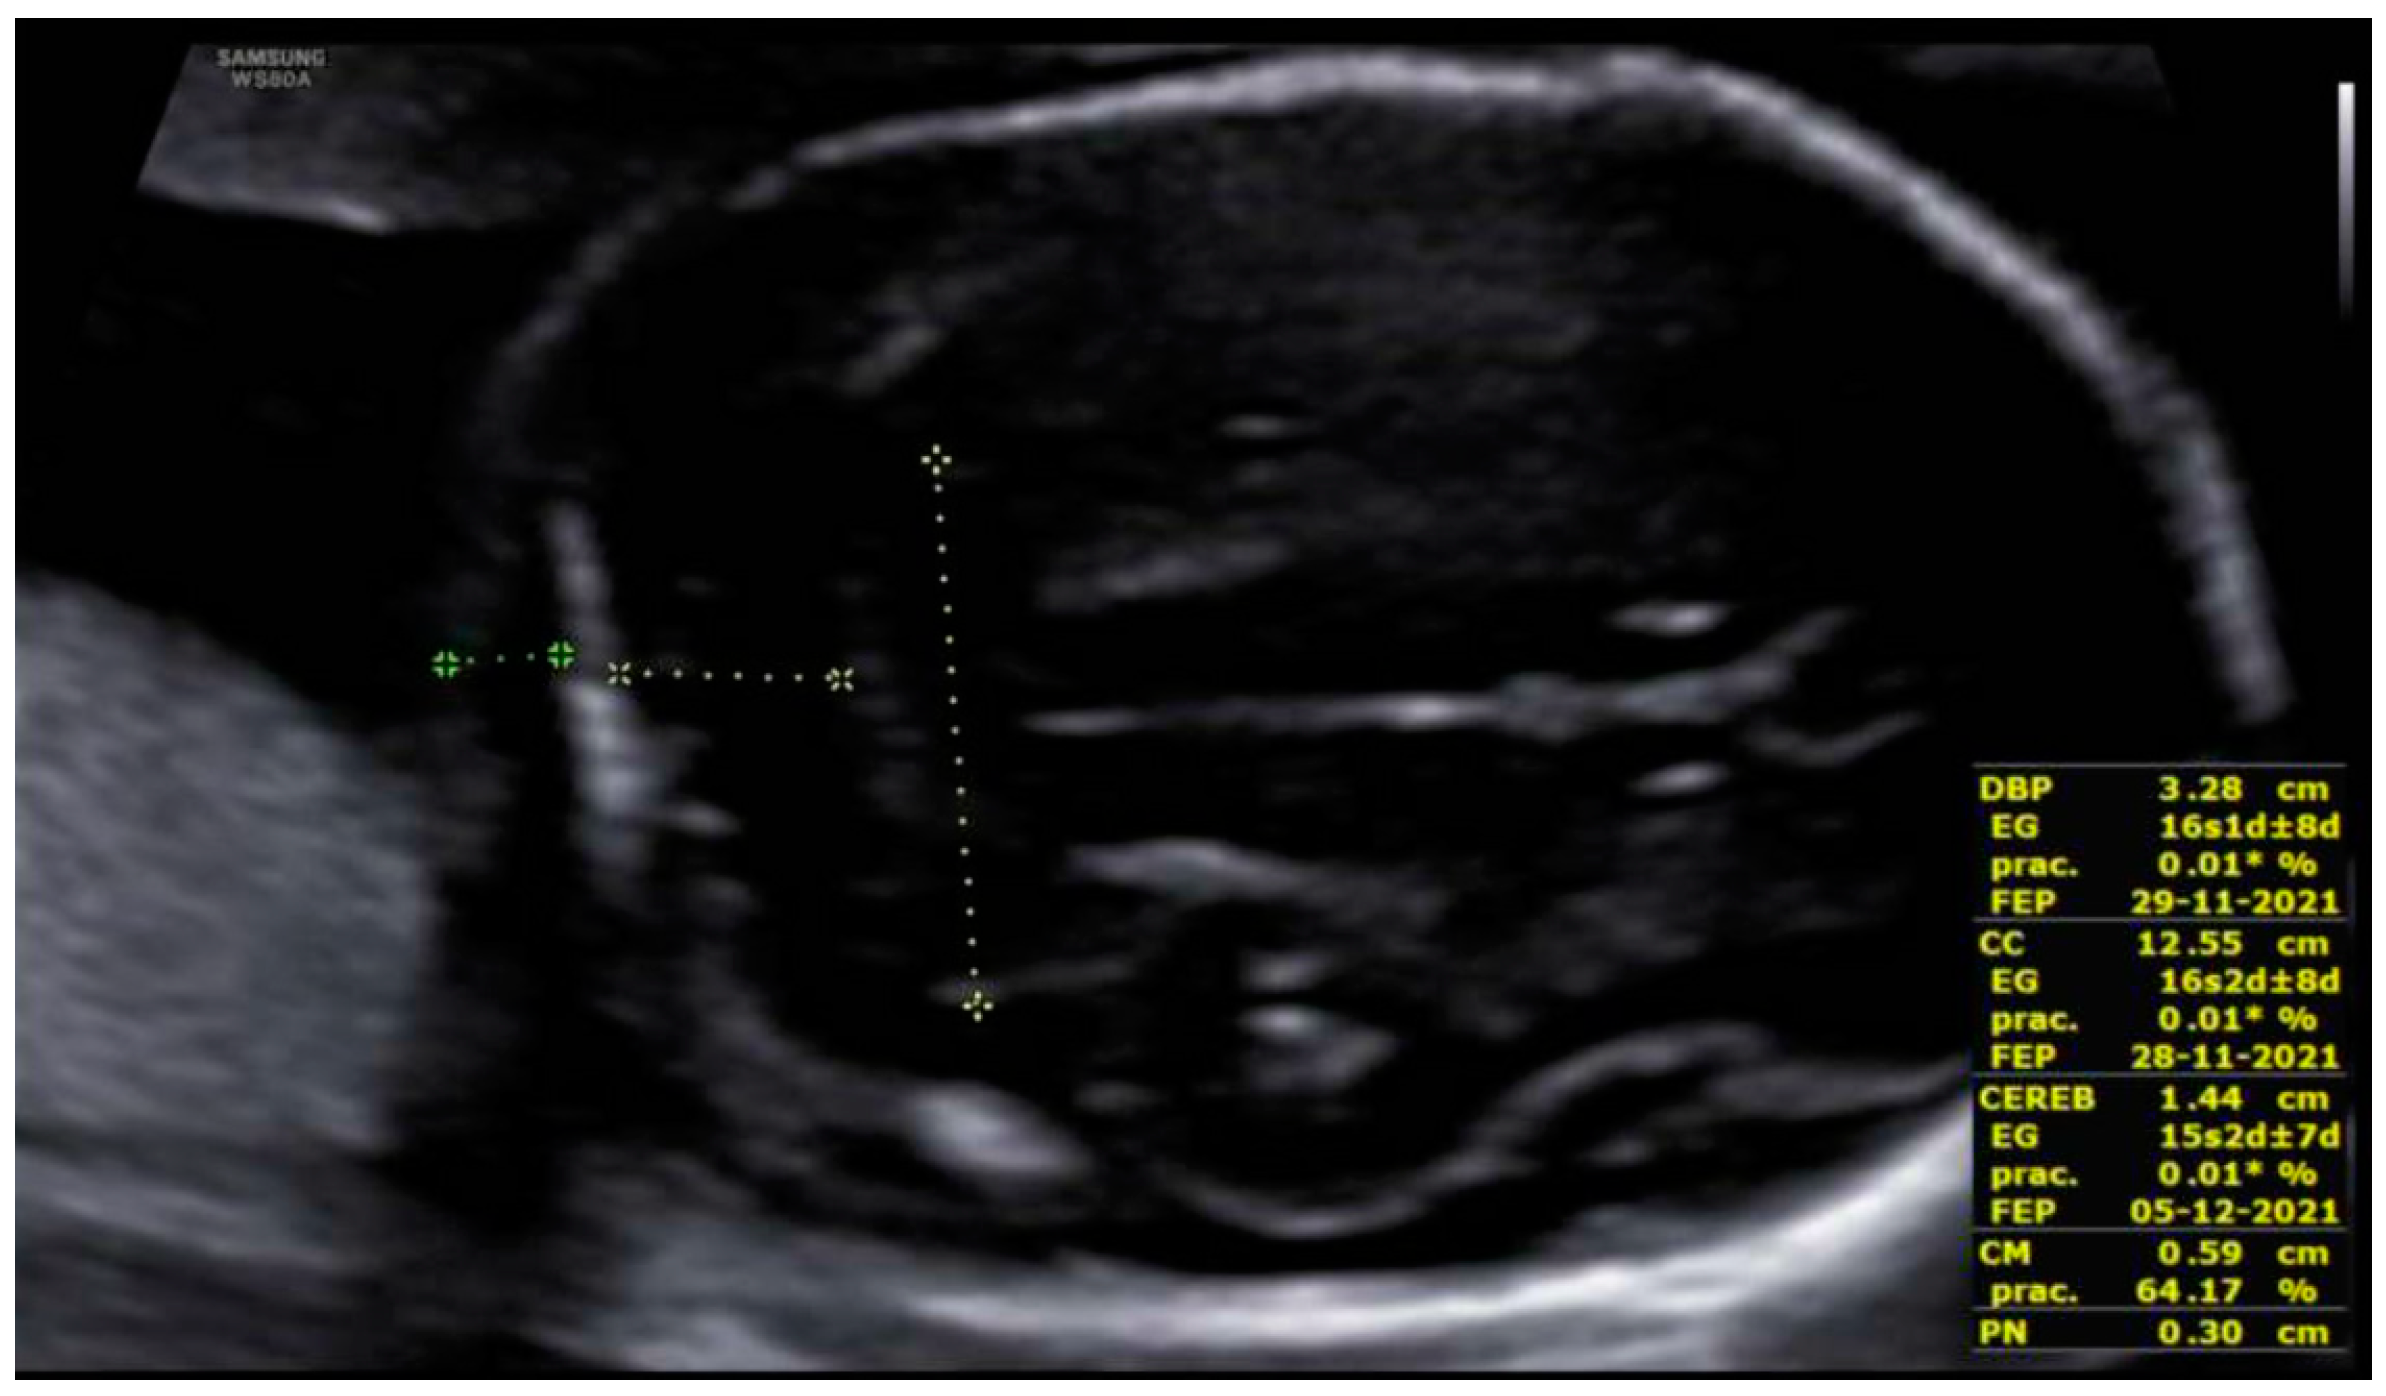

3. Results: Case Presentation